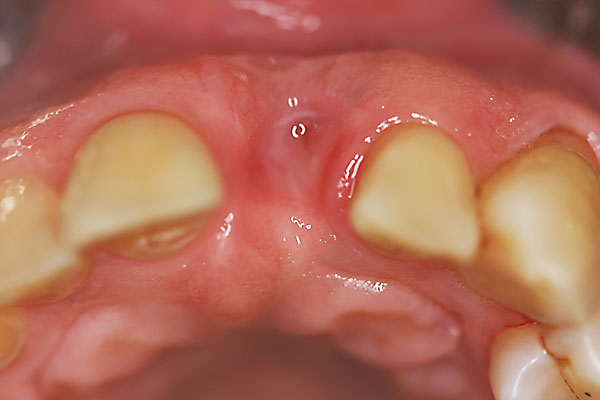

Fall: Einzelzahnlücke nach Zahnextraktion